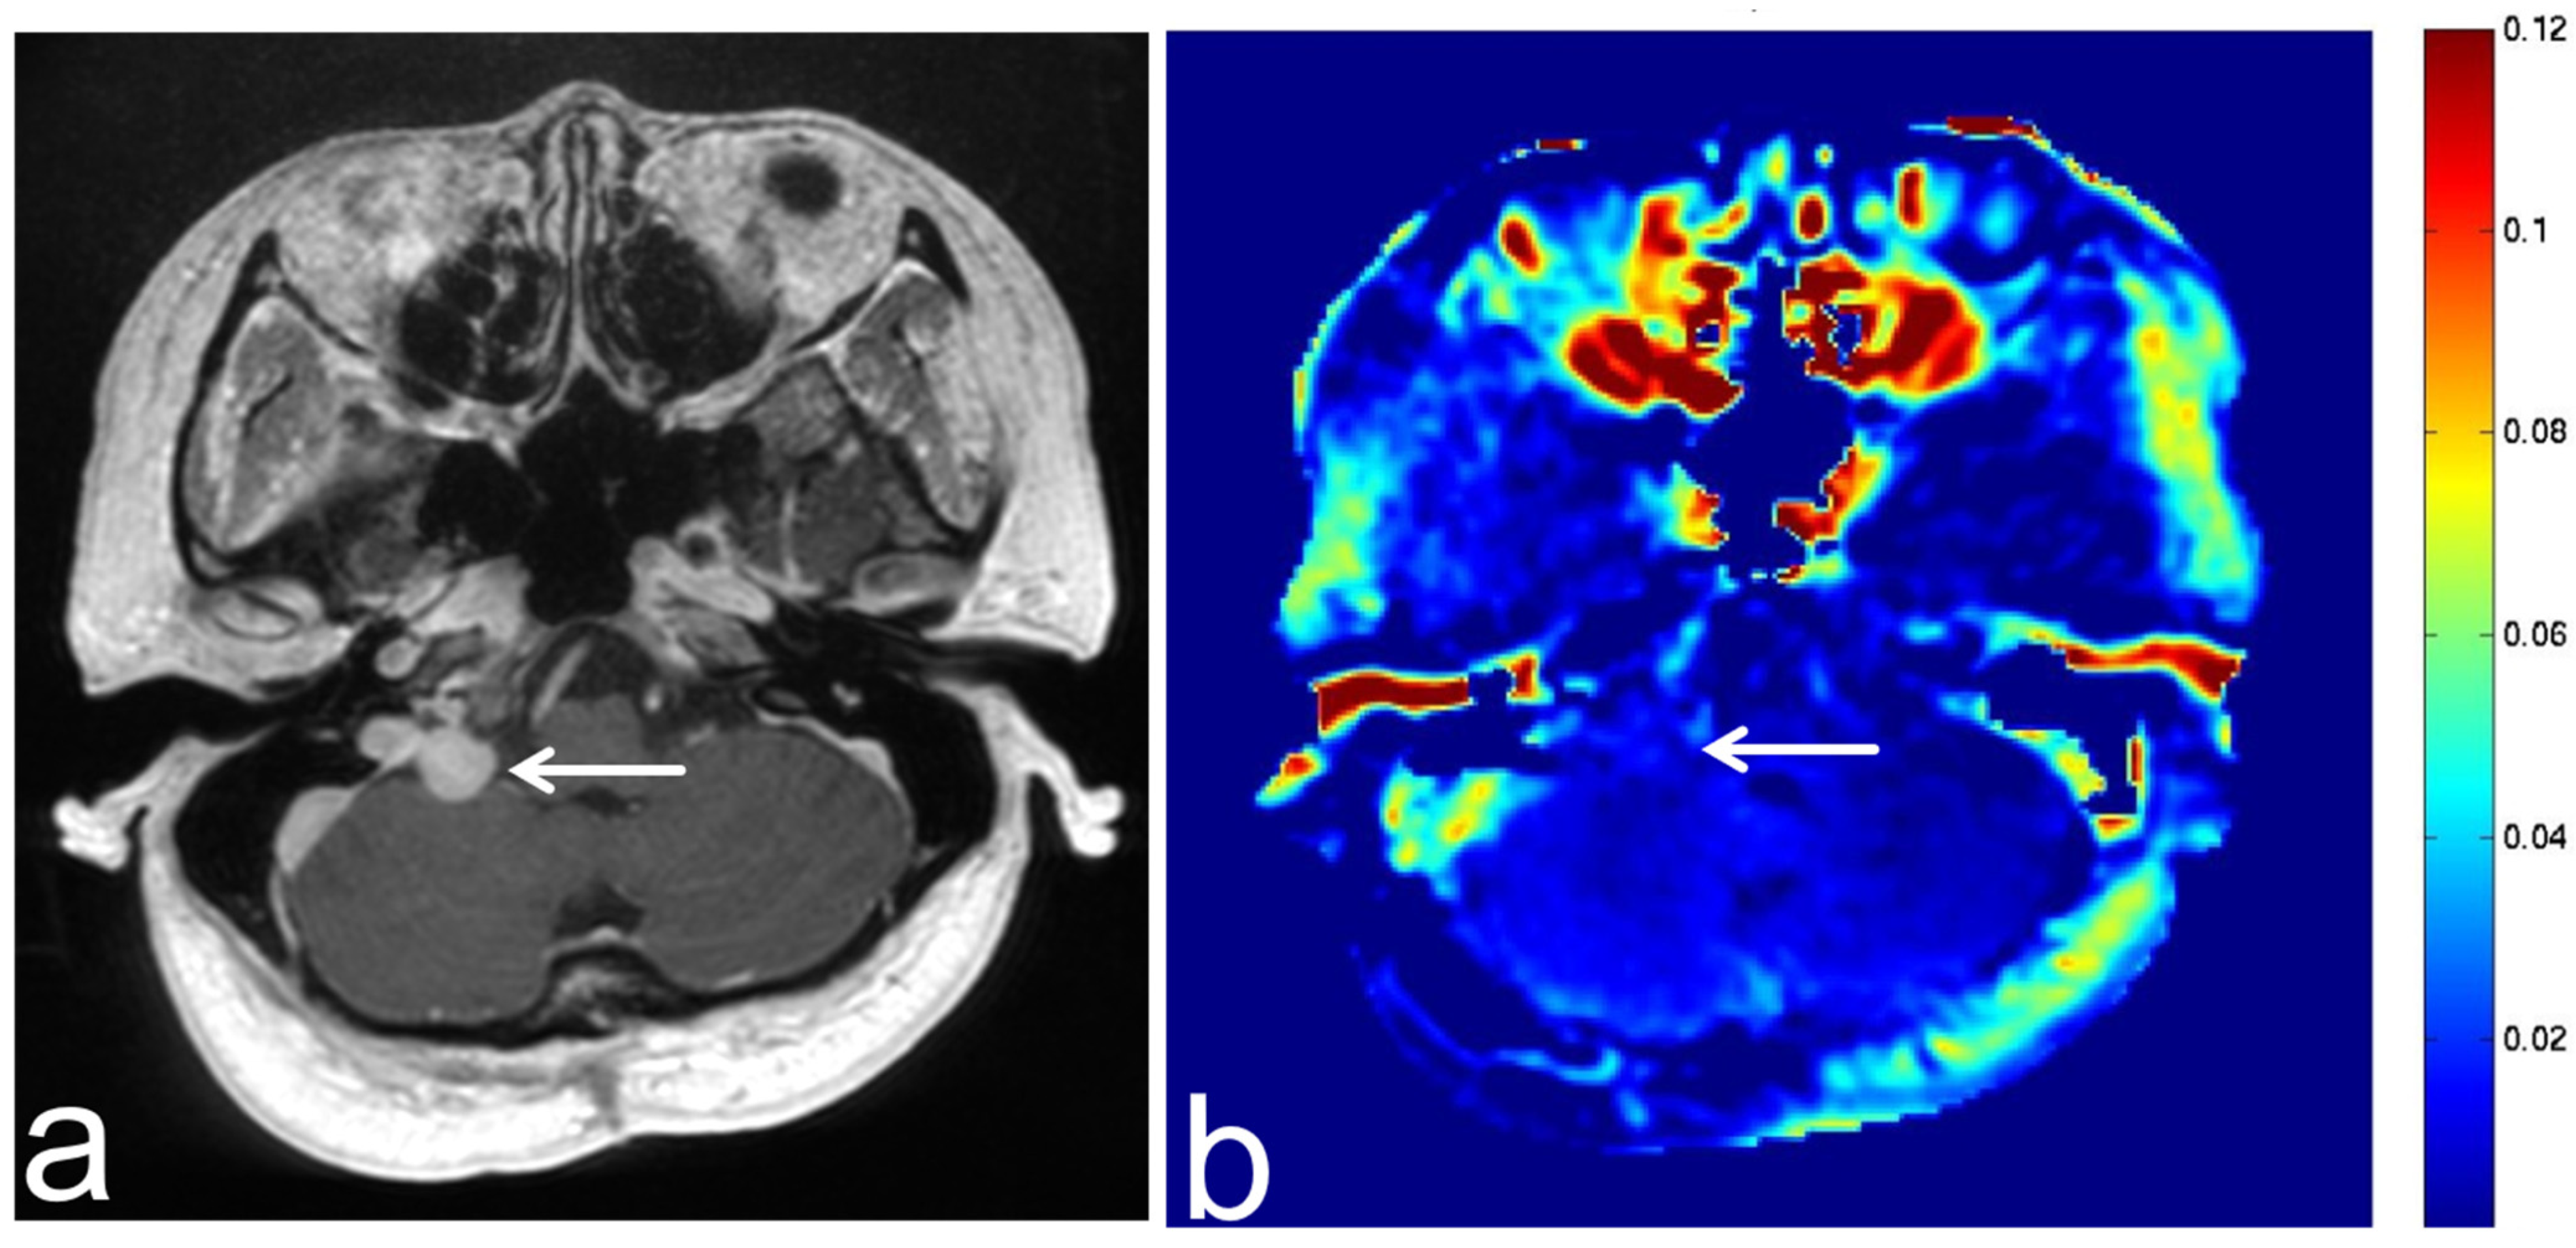

7.3. Schwannoma

7.4. Lipoma